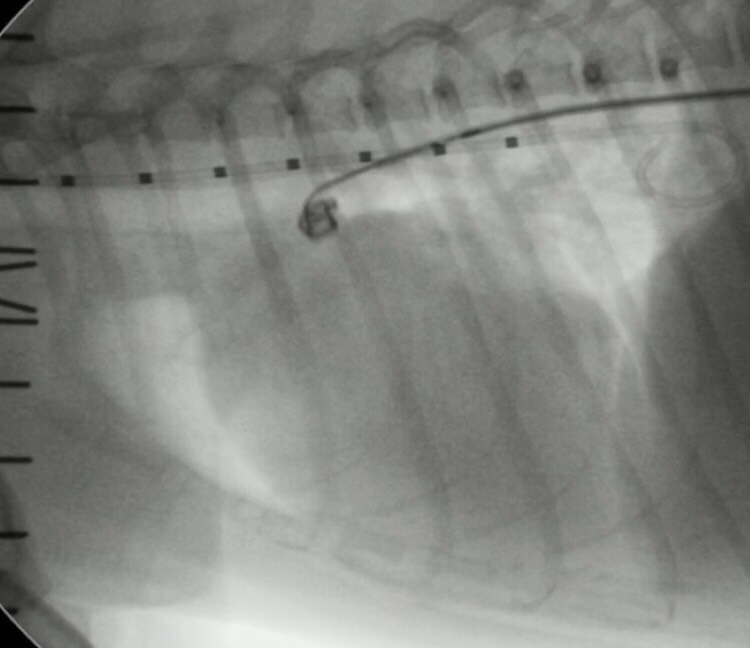

犬に動脈管開存症に対して心臓カテーテル手術を行なった症例

今回は健康診断で、心雑音が聴取され、各種検査で動脈管開存症と診断し心臓カテーテルでの手術を実施した症例を紹介させて頂きます。

今回、治療法としてコイル塞栓術を実施いたしました。

写真は、コイル塞栓の一連の流れを掲載させて頂きました。

症例は術後の短絡血流もなく無事に退院できました。